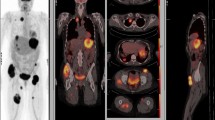

A deep understanding of these intricate interactions is crucial for devising treatments that can interrupt the metastatic process, such as drugs that block the enzymes cancer cells use to invade tissues, inhibit the growth of new blood vessels, or target the specific molecules and pathways cancer cells use to metastasize. These complicated pathways of cancer metastasis [7] may be depicted in Figs. 5 and 6.

Dichotomy of routes of cancer metastasis: one through the lymphatic vessels to the sentinel lymph nodes as the primary gateway and the other through the blood vessels directly to the distant sites. Permission has been obtained to reproduce this figure from Springer Nature from the cover image for the Special Issue of Clinical and Experimental Metastasis, Springer Nature, Volume 35, Number 5–6, 2018